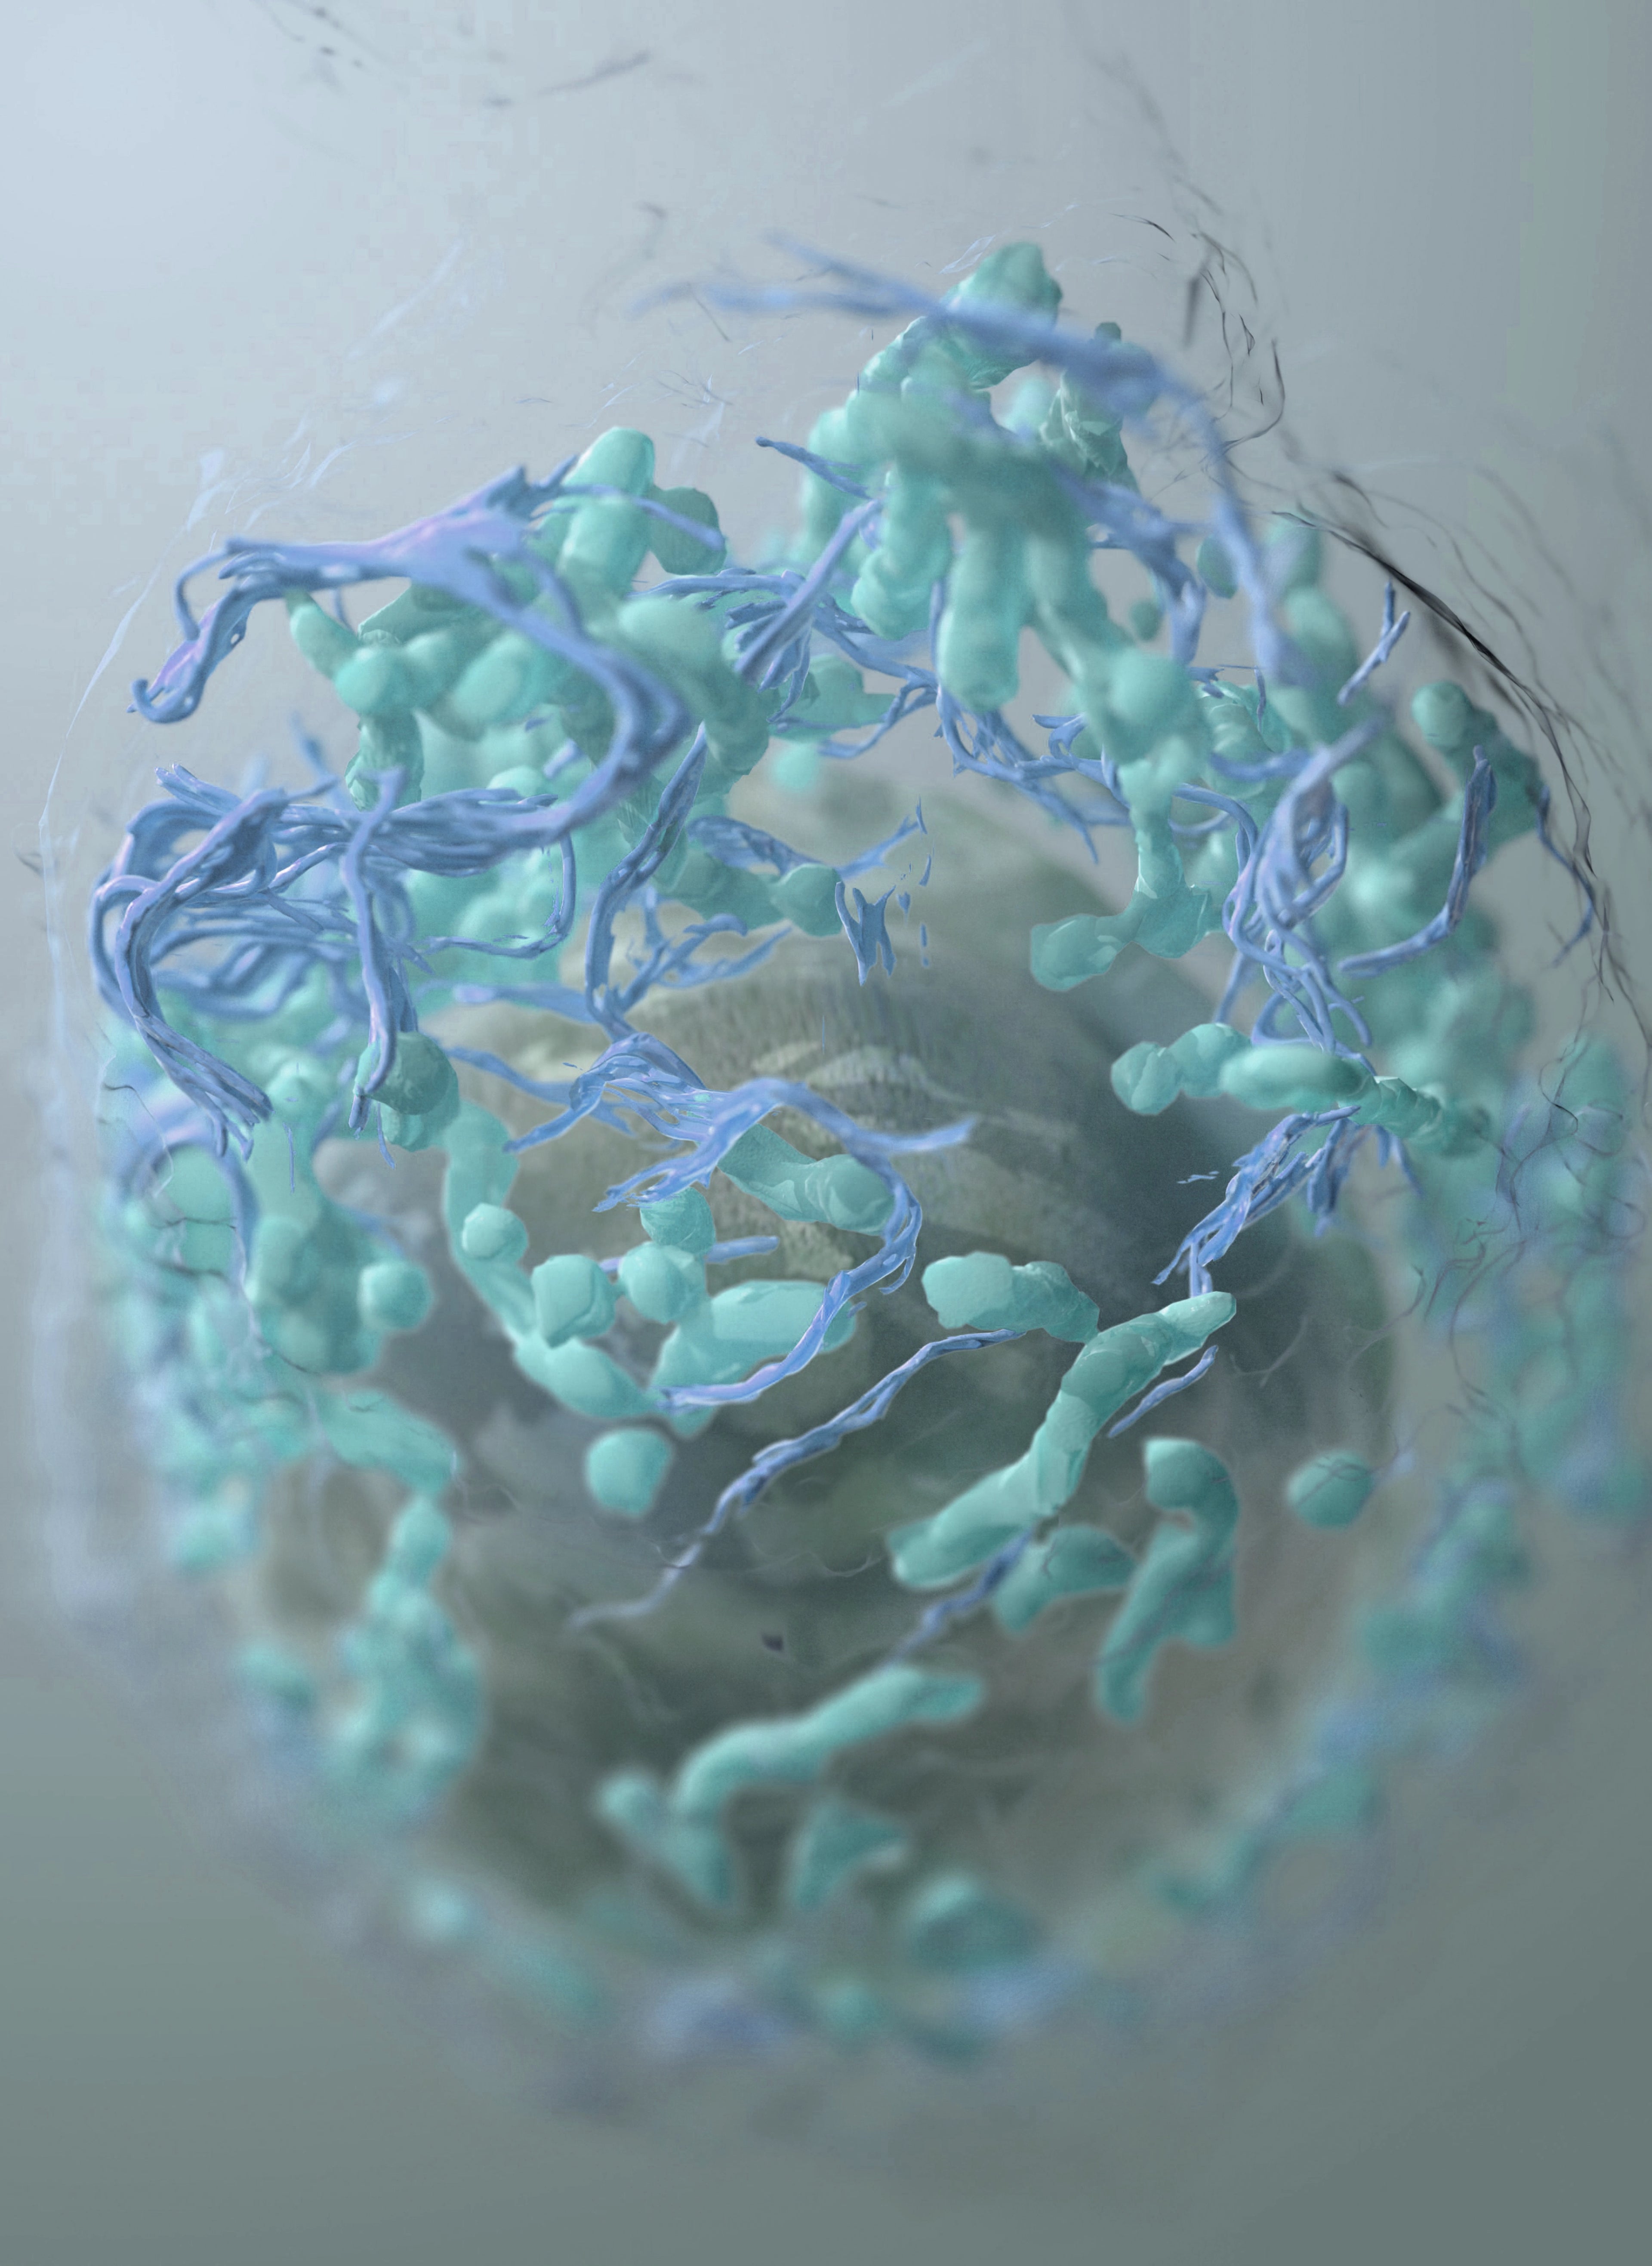

Das Spike-Protein verstehen

Das Spike-Protein spielt eine zentrale Rolle bei der Erkennung bestimmter Infektionen. Unser Test ermöglicht es, gezielt darauf zu prüfen und so fundierte Entscheidungen für Ihre Gesundheit zu treffen. Moderne Wissenschaft – einfach anwendbar.